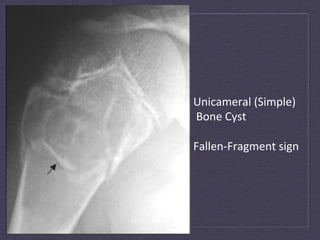

Unicameral  (Simple)    Bone  Cyst     Fallen-­‐Fragment  sign